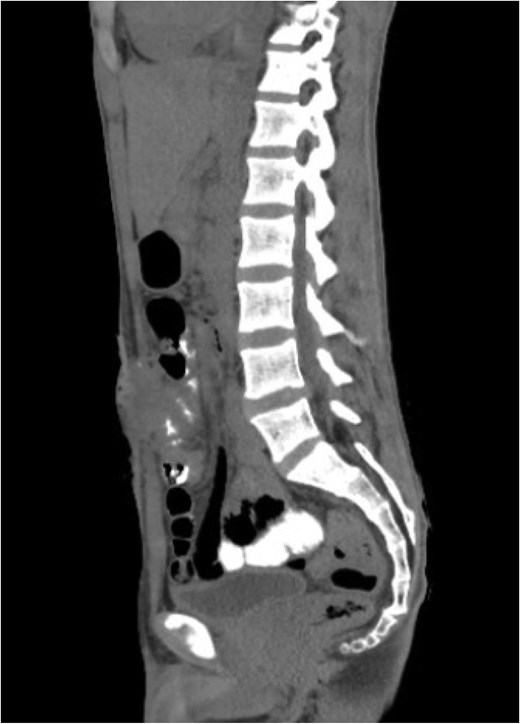

One week after surgery, the patient developed a surgical site infection with the development of a low-output enterocutaneous fistula (Fig. 2). The patient was treated conservatively with subcutaneous abscess drainage, antibiotics, diet modification, and wound care.

Sagittal view of abdominal and pelvic CT scan with IV and oral contrast shows anterior abdominal wall collection near the supra-umbilical wound with faint linear contrast within the collection representing enterocutaneous fistula.